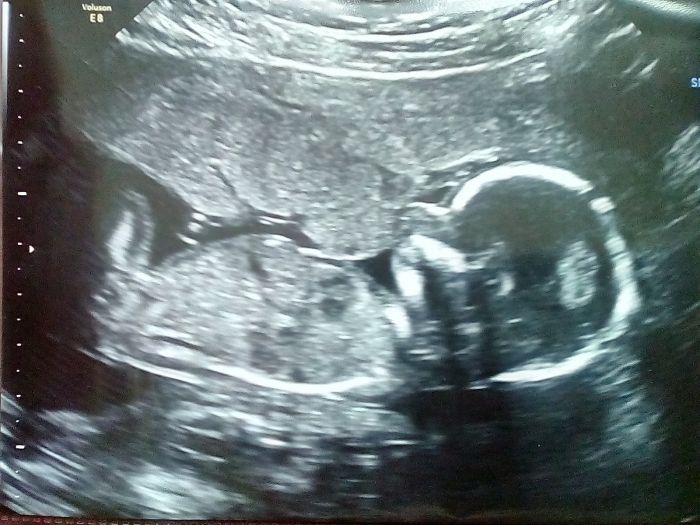

A ještě přidávám fotečku ze 27. dubna (aktuálnějsí nemám, pač se nechtěla nechat fotit - na ultrazvuku byla uložená sice krásně z profilu, ale měla otočenou hlavičku, takže by na fotce vypada spíš jako mimozemšťan

)